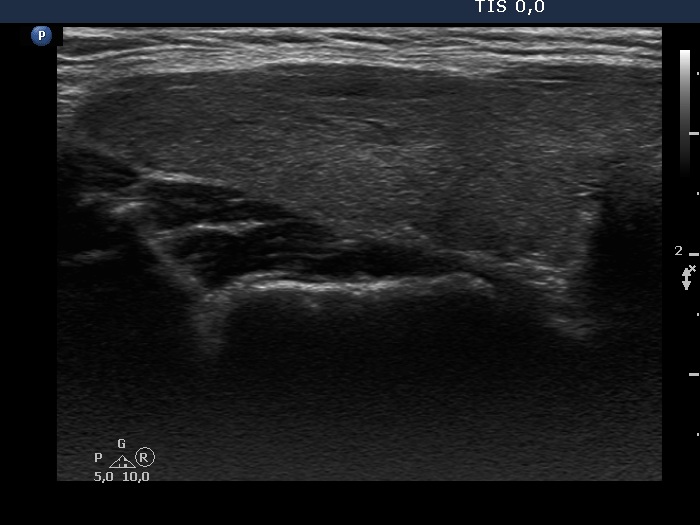

Consecutive patients with the final diagnosis of Hashimoto's thyroiditis - case 27 (389) (ultrasonographic picture 2)

Right lobe, longitudinal scan.